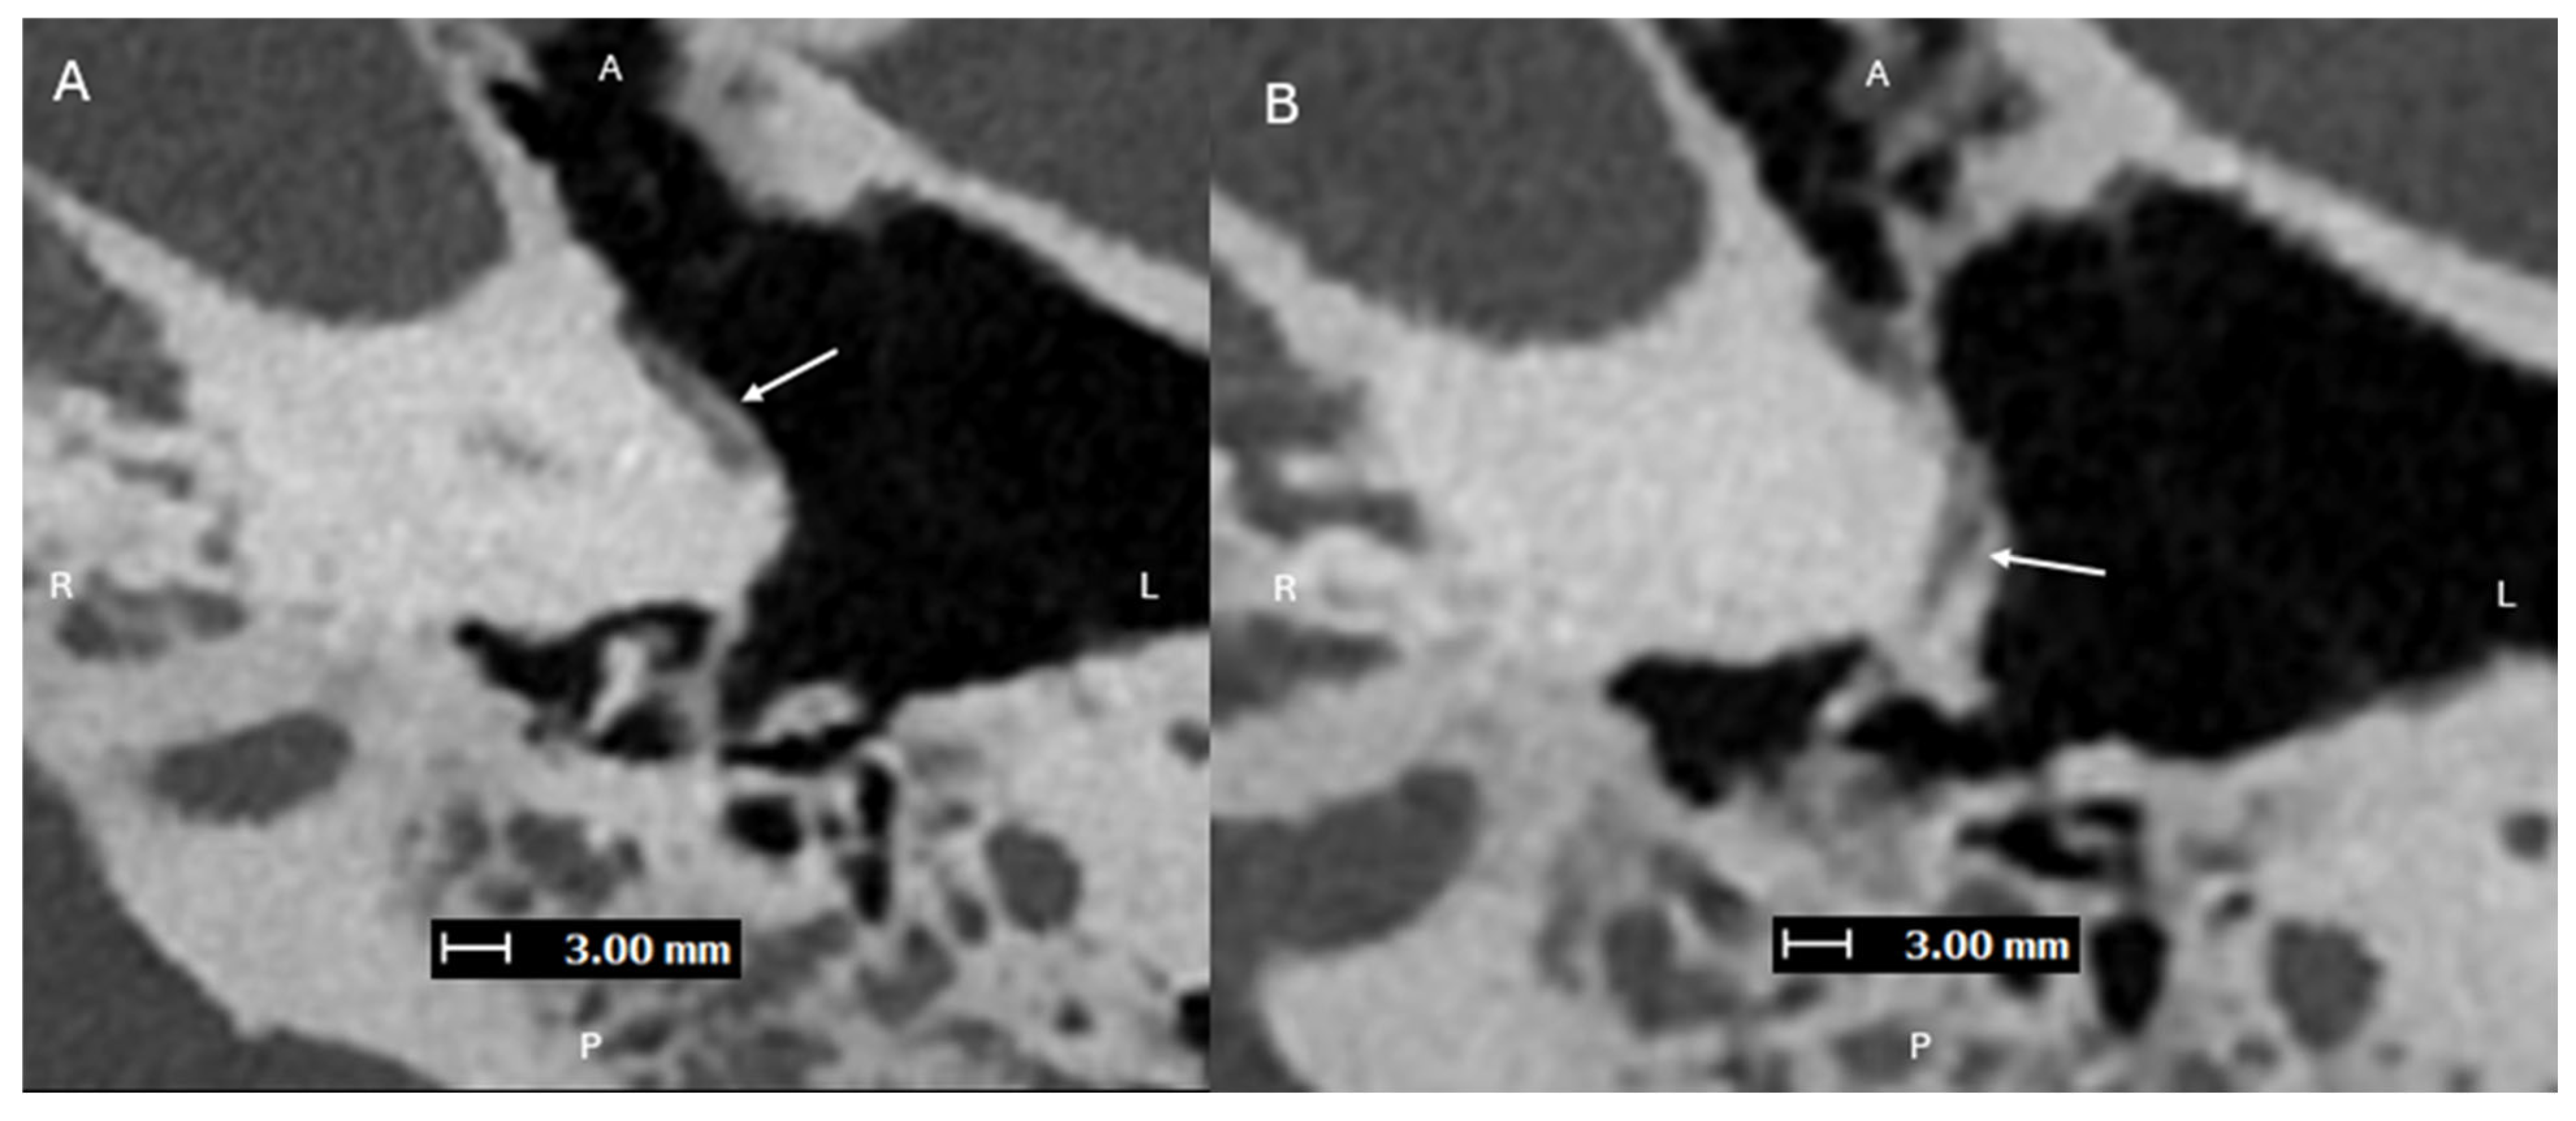

Figure 2. Axial images (superior to inferior (AD), with A, P, L, R for orientation donating anterior, posterior, left, and right respectively) from a PCD-CTA study—with UHR mode (Collimation 120 × 0.2 mm), Tube voltage (120 kVp), slice thickness/increment (0.2/0.2 mm), and sharp Kernel (Hv56) with Quantum Iterative Reconstruction (3)—demonstrating an aberrant L ICA (solid arrows) within an enlarged ITC (dashed arrows). Aberrant ICA are congenital vascular anomalies that occur from the involution of the cervical portion of the ICA, which leads to enlargement of the normally small collateral inferior tympanic and caroticotympanic (hyoid) arteries [1]. The segment most noted as the aberrant ICA is the inferior tympanic artery [2]. The inferior tympanic artery is a branch of the external carotid artery, usually the ascending pharyngeal artery, which extends through the inferior tympanic canaliculus (ITC), and is enlarged in the setting of an aberrant ICA [3]. As this artery courses along the cochlear promontory (via the ITC), no carotid plate separates the vessel from the middle ear cavity, and the vessel appears as a vascular retrotympanic mass on exam. It is very important to recognize an aberrant ICA on imaging. Accurately describing the presence of this aberrant vessel is important to help prevent iatrogenic injury during intervention of the middle ear. While typically asymptomatic in some cases, it can present with hearing loss and sometimes pain [4,5]. An aberrant ICA is commonly included in the differential diagnosis for vascular middle ear masses with other entities such as lateralized ICA, dehiscent jugular bulb, aneurysm of the petrous ICA, glomus tympanicum tumors, and glomus jugulare tumors [6,7].